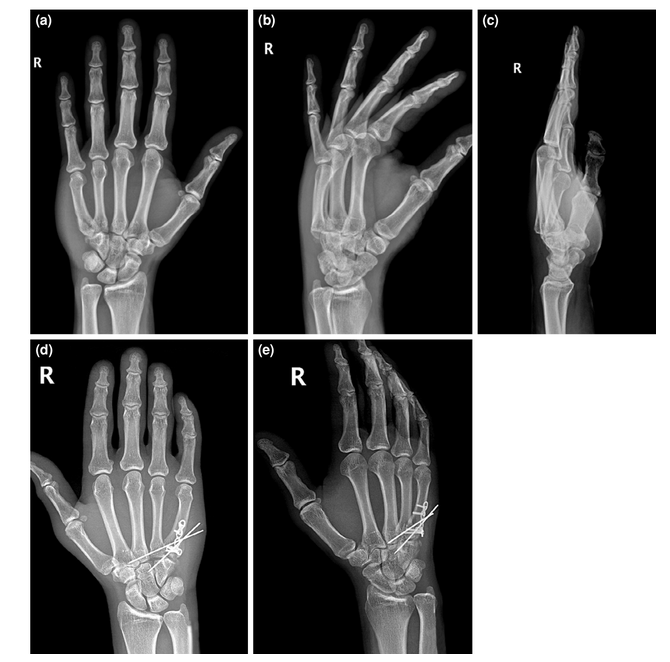

手术治疗患者的术前和术后影像;一个附加关节桥接k线钢板固定的例子。(a-c)术前AP、斜位和侧位x线图像。(d, e)术后AP和斜位x线图像。